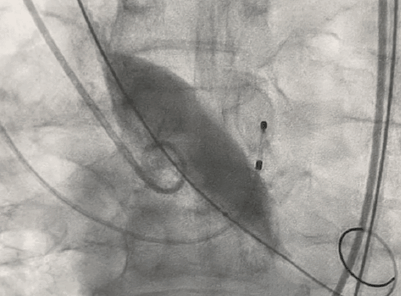

瓣膜定位

瓣膜释放后形态位置良好,造影无返流

术后即刻评估: